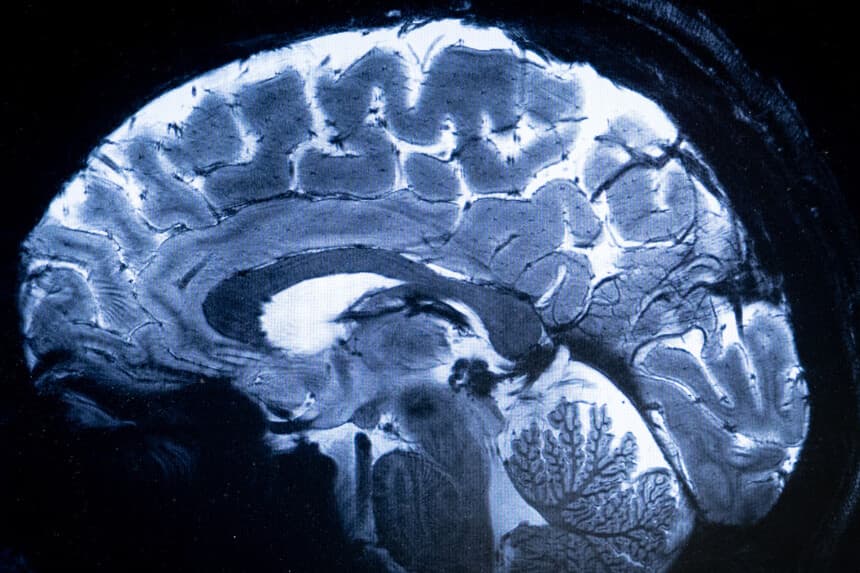

Los hallazgos provienen de 4216 imágenes de resonancia magnética que abarcan edades comprendidas entre los 0 y los 90 años. Las imágenes proceden de conjuntos de datos de la Universidad de Carolina del Norte en Chapel Hill, la Universidad de Minnesota y la Unidad de Cognición y Ciencias del Cerebro del MRC de la Universidad de Cambridge.